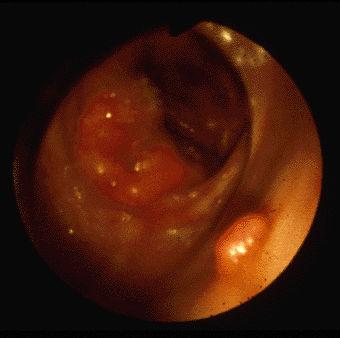

Semiannular carcinoma and small sessile polyp in the cecum. Right side tumors are often detected in HNPCC patient.

Malignant epithelial tumor/Adenocarcinoma

Large intestine(Colon)/Cecum

Endoscopy

Type 2 Ulcerated type with clear margin/

40 -